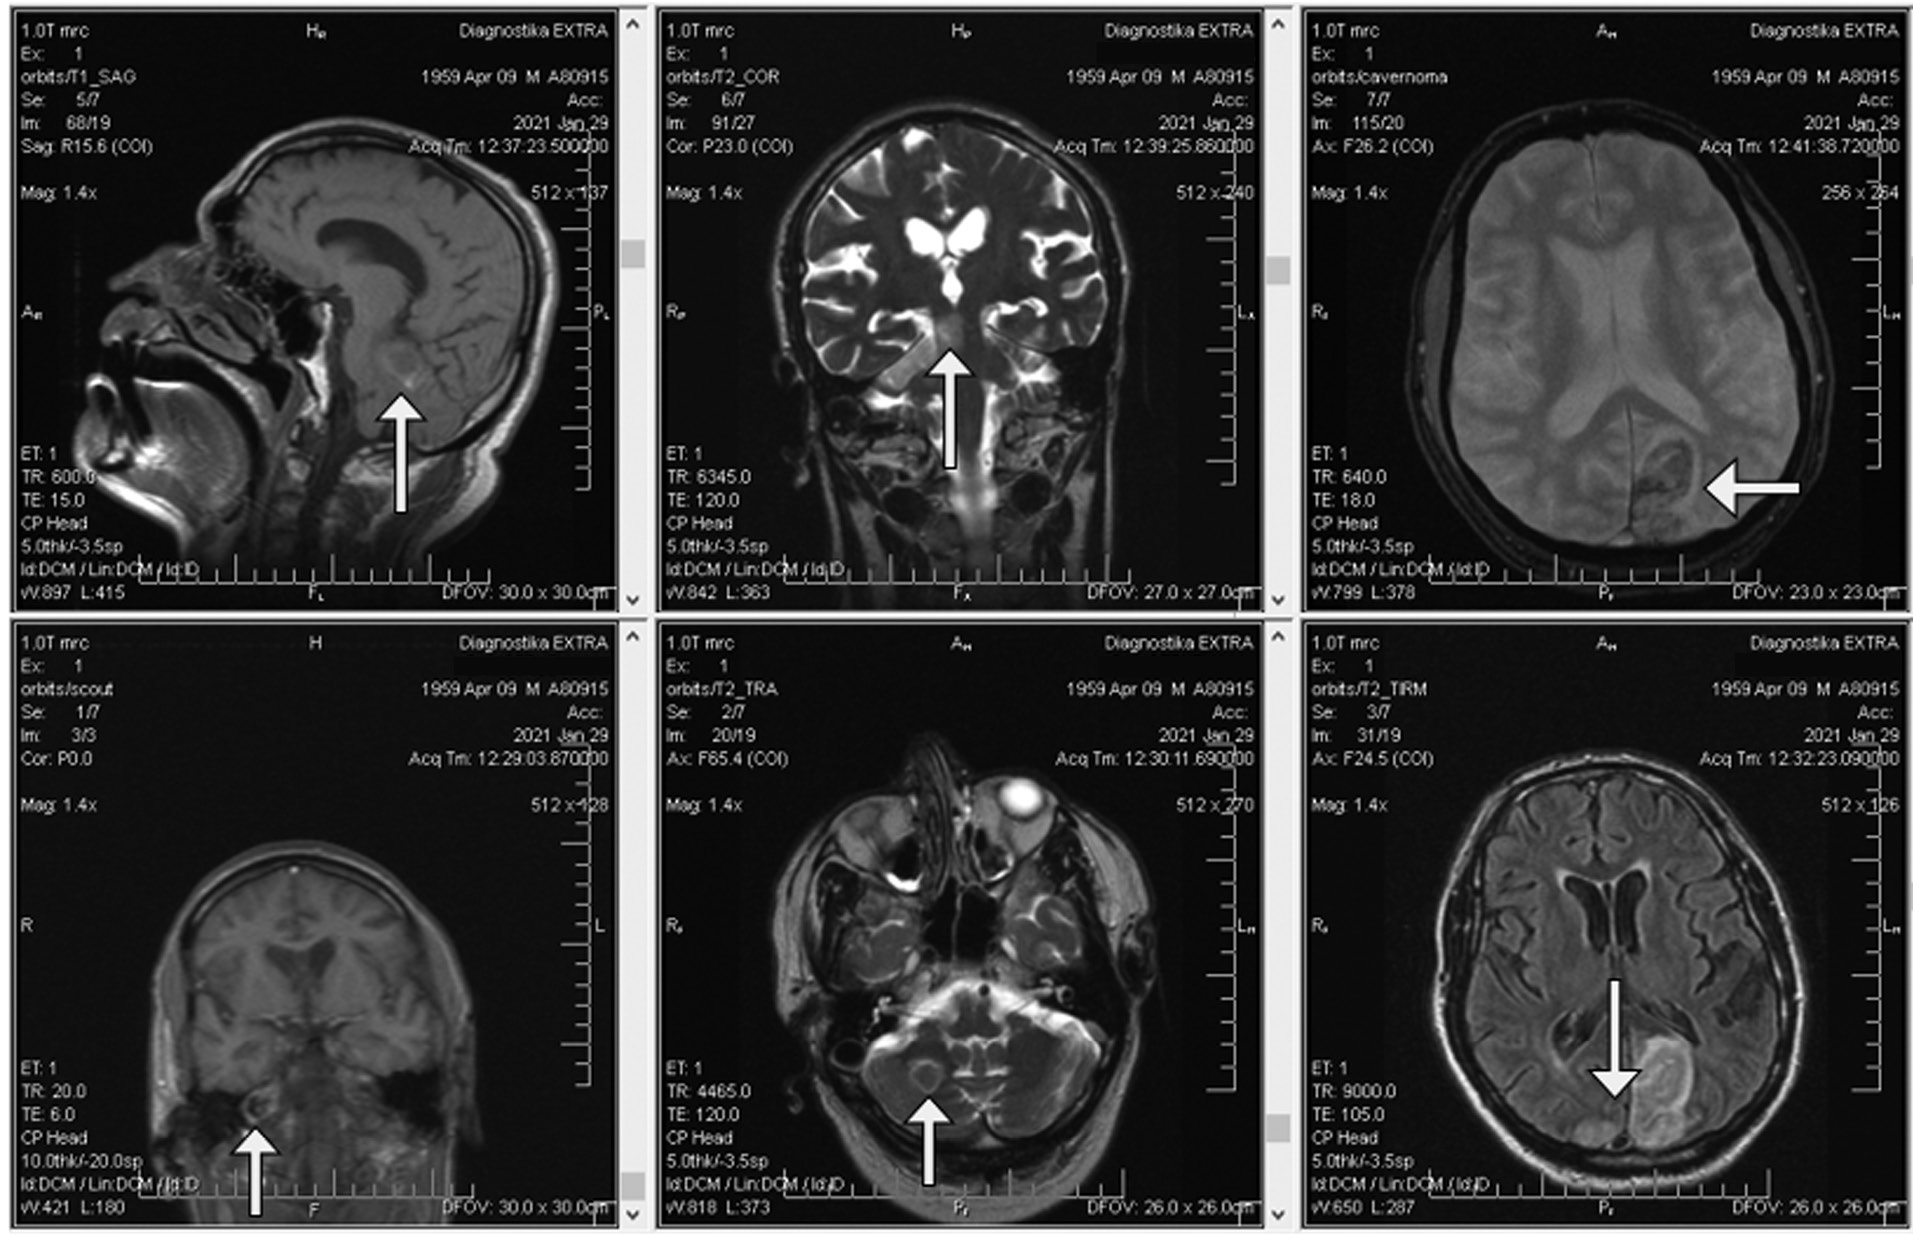

Краниопатии. Дебютирующие в остром периоде заболевания нарушения обоняния, вкуса, зрения и слуха чаще всего обратимы в течение первых 3 нед. [4, 28, 29]. Отсутствие или частичное восстановление системы чувств наблюдается при воспалительных невропатиях I, II, IV, VII, VIII черепных нервов [30-34], ятрогенном повреждении X, XII нервов (синдром Тапиа) после интубации трахеи [35]. Вовлечение в патологический процесс II, III, V, VI нервов возможно при тромбозе кавернозного синуса [36], III, VII, IX, X, XII — при стволовом инсульте (собственное наблюдение; рис. 1), аутоиммунных осложнениях (синдромы Гийена-Барре, Миллера Фишера) [37, 38], X — при сенсорной ларингеальной невропатии (sensory laryngeal neuropathy, SLN) [39], постинфекционной вирусной вагусной невропатии (postviral vagal neuropathy, PVVN), клинически проявляющихся в виде упорного, толерантного к терапии кашля, купируемого при назначении амитриптилина, габапентина [40, 41].

Fig. 1. Arterio-arterial cerebral embolism of basial artery branches. Right-side hemi-syndrome of the brainstem, cerebellum. Asymmetric infarctions of occipital lobes.